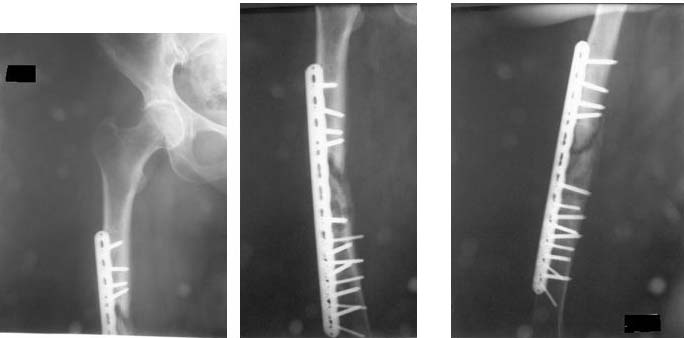

Мое удивление не только к количеству винтов, но и к их "качеству" .

Блокированные винты в прямой немоделированной диафизарной пластине должны быть параллельны друг другу и введены в определенную часть 8-образнеого отверстия. В проксимиальном отломке, похоже, толко один винт (самый

проксимальный) введен корректно остальные 3 не пойми как. В дистальном отломке угадывается только 2 корректно установленных блокированных винта...

С уважением, А.Семенистый.

Результат нашего лечения: Произведено удаление пластины МIPO. Интрамедуллярный остеосинтез с рассверливанием канала. На 2-е сутки после операции больная передвигается при помощи костылей, с полной нагрузкой на оперированную конечность, болей в области перелома нет.

Фотографии в приложении.

Скажите пожалуйста, а зачем гвоздик заперт статически? Динамическая фиксация здесь более подходит.

Я не предполагаю, я в этом твердо убежден. Статическое блокирование диафизарных переломов показано в ситуациях,когда есть опасения в сохранности длины конечности в условиях осевой нагрузки: при многооскольчатых, косых, винтообразных переломах. Также показанием являются все свежие переломы, поскольку возможно наличие трещин невидимых на рентгене. В данном случае канал рассверлен, диаметр гвоздя хорошо подобран - в статической фиксации нет никакой необходимости, угрозы укорочения на гвозде нет и в помине. Снимается нагрузка с конструкции,не будет перелома винтов. Более того динамическая фиксация в таких случаях уже не более чем через месяц на снимках радует глаз вполне очевидным регенератом.

В недавней дискуссии по поводу "нужна ли динамизация в большинстве случаев" мои оппоненты и одновременно ее(динамизации) противники ссылались на свой личный опыт и один (!) авторитетный не самый свежий учебник, уповали на то, что крайне трудно найти работы по данной теме в доступных публикациях. Ради любопытства в пабмеде за одну минуту я нашел только свежих полнотекстовых статьи 3 штуки (про абстракты вообще молчу). Так вот к факторам, существенно затягивающим сращение диафизарных переломов относится диастаз между отломками более 3 мм (сравниваются статическая и динамическая фиксация). Так вот на снимках как раз такой диастаз - более 3 мм.